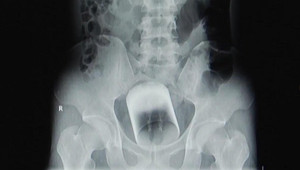

Ảnh chụp X-quang cho thấy chiếc cốc thủy tinh có đường kính 7cm, cao 8cm, nằm ở phần trên trực tràng và có thể khiến người đàn ông mất mạng nếu không được lấy ra kịp thời.